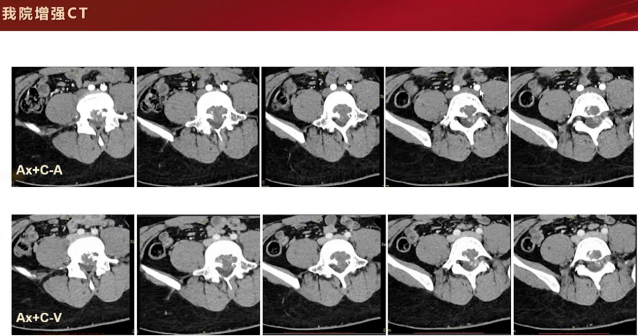

增强CT检查,在骨窗和软组织窗下可见L5后缘局部膨胀性骨质破坏,内缘呈扇贝样压迹改变,仍无明显骨膜反应。平扫时,病灶内可见斑斑点点高密度影,性质待定,可能为残存骨嵴、软骨源性钙化或骨化表现。该病例主要累及L5椎体,附件未见明显受累。增强扫描呈轻度强化,矢状位和冠状位可见病灶主要累及椎体,未累及附件。